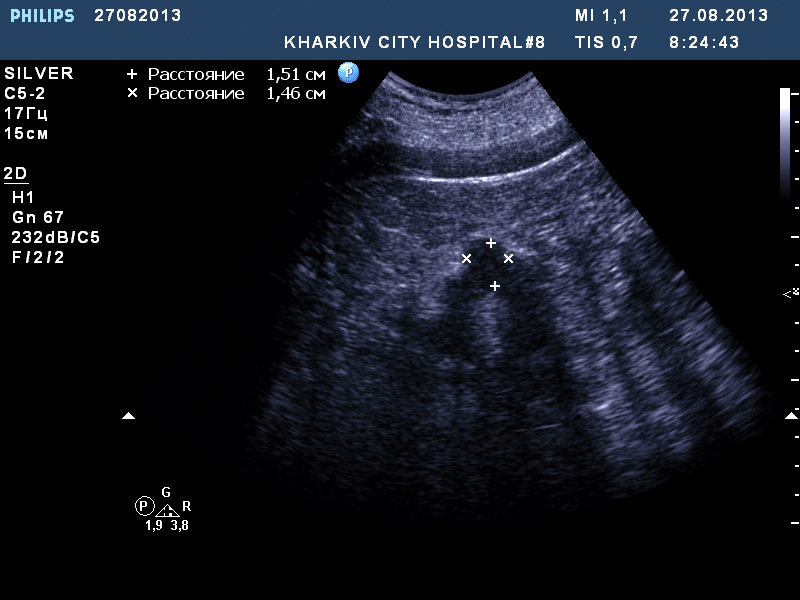

собственно такая картина.

если мой прицел не сбился, вероятно ПКР.

Рекомендовал КТ.